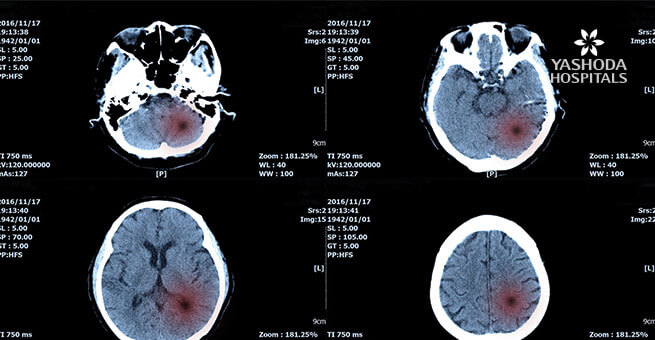

CT scan of the head: These scans help in getting a more detailed scan of the body than an X-Ray and can be done with or without contrast. A special dye is used in the CT scan that helps the doctors in seeing some structures like blood vessels more clearly.

MRI of the head: A special dye is used in the MRI and helps in detecting tumors. MRI is different from a CT scan because it is done without radiation and helps in providing a detailed picture and structure of the brain itself.